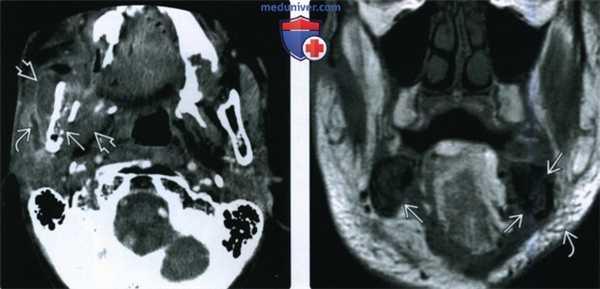

(Слева) При аксиальной КТ в костном окне визуализируется очаг литического характера с нарушением целостности кортикальной пластинки нижней челюсти слева. Возле корней моляров нижней челюсти слева определяются участки «просветления». Изменения (незаживающая язва, обнажение кости, а также факт использования бисфосфонатов) позволяют сделать заключение об остеонекрозе.

(Справа) При аксиальной КТ в костном окне определяются типичные признаки остеонекроза нижней челюсти, обусловленного внутривенным введением бисфосфонатов. Обратите внимание на очаг смешанного (склеротического и литического характера) в теле нижней челюсти слева в месте недавней экстракции зуба.

(Слева) При МРТ Т1ВИ в аксиальной проекции у пациентки, находящейся на лечении бисфосфонатами по поводу рака молочной железы, с жалобами на боль в области челюсти, определяется отек нижней челюсти справа с сигналом низкой интенсивности, тогда как слева сигнал в коаном мозге не изменен. Определяется также перифокальное воспаление мягких тканей.

(Справа) Корональная КТ в костном окне, признаки тяжелого остеонекроза и дстарукции верхней челюсти у пациента с множественной миеломой (после внутривенного введения бисфосфонатов). Обратите внимание на костный секвестр. Определяется снижение пневматизации верхнечелюстной пазухи, которое, скорее всего, не связано с остеонекрозом.